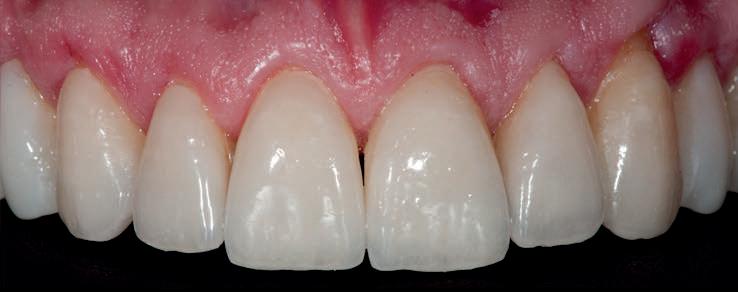

locaţii grefate. Implanturile plasate în această primă fază au fost încărcate cu bonturi conice şi, în unele cazuri, cu omologii lor angulaţi (fig. 16, 17).

S-au selectat bonturi standard de titan pentru a evita schimbarea sau refrezarea bonturilor individualizate mai scumpe; în plus nu necesită utilizarea cimentului temporar în proximitatea sau în jurul locaţiilor chirurgicale, întrucât utilizează doar şuruburi pentru retenţie.

Atitudine: Până la dobândirea vindecării totale a ţesuturilor şi a implanturilor secundare s-au utilizat bonturi standard de titan. Fig. 18 prezintă bonturile individualizate maxilare şi mandibulare aplicate iar fig. 19 un prim-plan al cadranelor de partea dreaptă a pacientului, afişând finalizarea cazului la 15 luni după începerea tratamentului iniţial. Recesiile se pot obiectiva corespunzător 1.4. şi 1.3. În acest caz, s-a încercat minimizarea susceptibilităţii la recesie prin implicarea bonturilor temporare standard fixate cu şurub în cursul fazelor de vindecare pe toată durata etapelor iniţiale ale tratamentului.

În pofida acestor eforturi, totuşi, recesia a apărut în anumite regiuni unde implanturile erau plasate vestibular. Ulterior, s-a încercat grefarea ţesutui moale din jurul locaţiilor cu recesie, dar fără succes.

Rezultatul final al cazului 5 (fig. 19) prezintă recesie vestibulară de peste 2mm în jurul bonturilor cu sprijin implantar, fiind evidentă prezenţa unui ţesut moale foarte redus din cauza plasării vestibulare a implanturilor. Butler, Kinzer susţin premiza că trebuie să existe suficient volum osos vestibular, chiar şi atunci când implantul este plasat ideal, multe complicaţii fiind legate mai degrabă de poziţia implantului.

Cazul (5):

Bonturi conice utilizate ca bonturi temporare

Figurile

16, 17. Implanturile din prima etapă încărcate cu bonturi conice şi, în unele cazuri, omologii angulaţi.

18. Bonturile individualizate inserate.

19. Rezultat final la 15 luni după începerea tratamentului iniţial.

şi va induce resorbţie osoasă şi migraţia apicală a ţesutului (Saadoun & Touati). Dacă implantul nu este plasat mai palatinal şi la 3-4mm apical de marginea gingivală liberă pentru a asigura profilul de emergenţă adecvat, rezultatul estetic este compromis (Chu et al). Un studiu de 2 ani a demonstrat că implanturile poziţionate anterior au demonstrat o recesie uşor mai accentuată, decât implanturile posterioare (Bengazi et al). Plasarea vestibulară a implanturilor se poate vizualiza clar în cazul 5 (fig. 17) cu bonturile de vindecare în poziţie.

Proximitatea implanturilor adiacente

Se recomandă existenţa a cel puţin 3mm de os între două implanturi adiacente (Tarnow et al). În acelaşi caz 5, corespunzător 2.5. şi 2.6. distanţa la nivel inter-implantar este sub 2mm iar între bonturi sub 1mm (fig. 17). Întrucât ţesuturile inter-implantare nu au acelaşi nivel de suport ca în cazul dinţilor naturali, distanţa interdentară devine esenţială în anticiparea poziţiilor finale ale ţesutului moale.